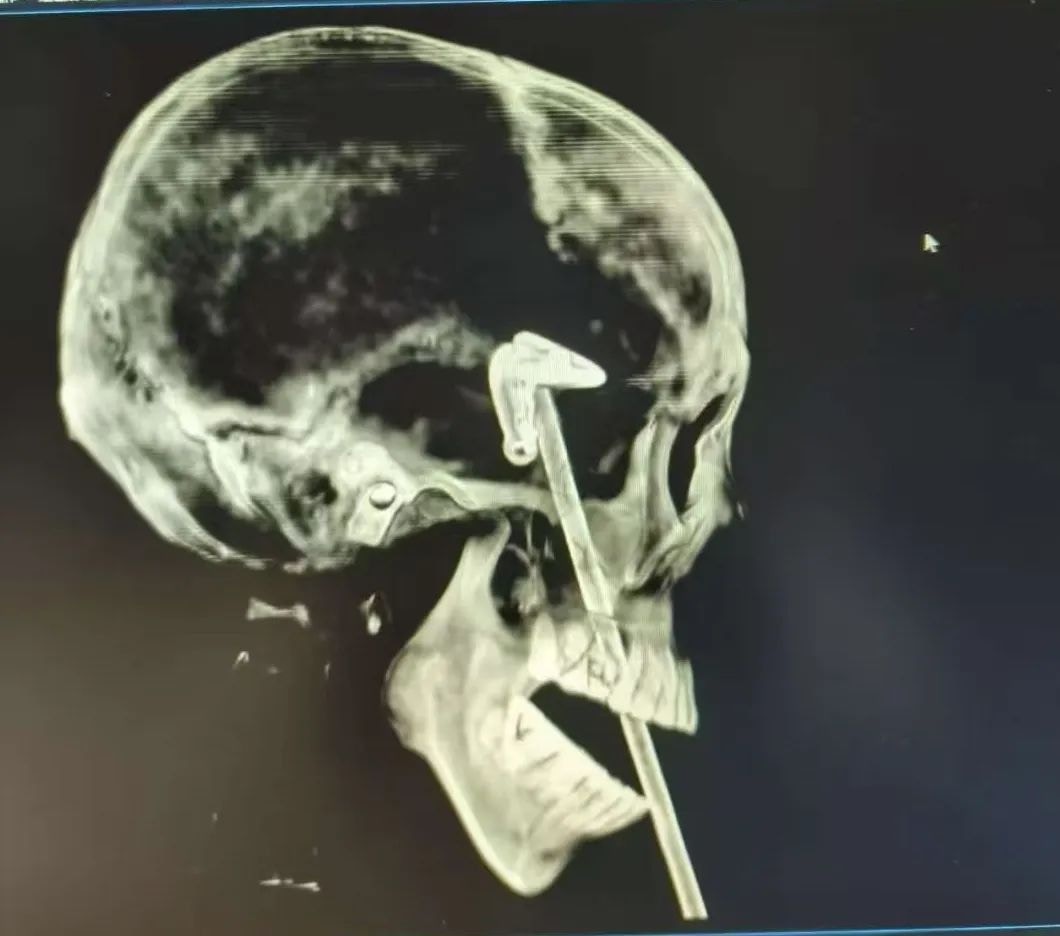

3 M! z' H% U! L8 U/ ECT圖。(南方都市報)

近日,深圳一名男子凌晨聚餐後,因醉酒向前摔去,正好摔在桌上擺放的長桿黑色金屬便簽夾上,長約42cm金屬桿從口腔插入,經過鼻子、眼窩,一路直直杵進大腦。: \3 X" _8 |" d

+ l; l: A/ @% d& ?1 nTVBNOW 含有熱門話題,最新最快電視,軟體,遊戲,電影,動漫及日常生活及興趣交流等資訊。緊急送醫後,經過長達10小時的手術,男子腦內的金屬桿被完整取出。據介紹,該金屬桿從嘴巴到顱內的長度,就超過了15厘米。

3 U: s' R0 o& I" mCT圖。(南方都市報)

接診的醫生表示:「這種貫通傷極為罕見,金屬異物攜帶大量細菌,且路徑涉及口腔、眼眶、顱腦等多個關鍵區域,稍有不慎就可能致命。」且金屬桿插入的部位特殊,插入顱內的尖端還連帶有一個金屬夾子,都給手術帶來了挑戰。公仔箱論壇4 _: \. o3 S6 V9 @% W